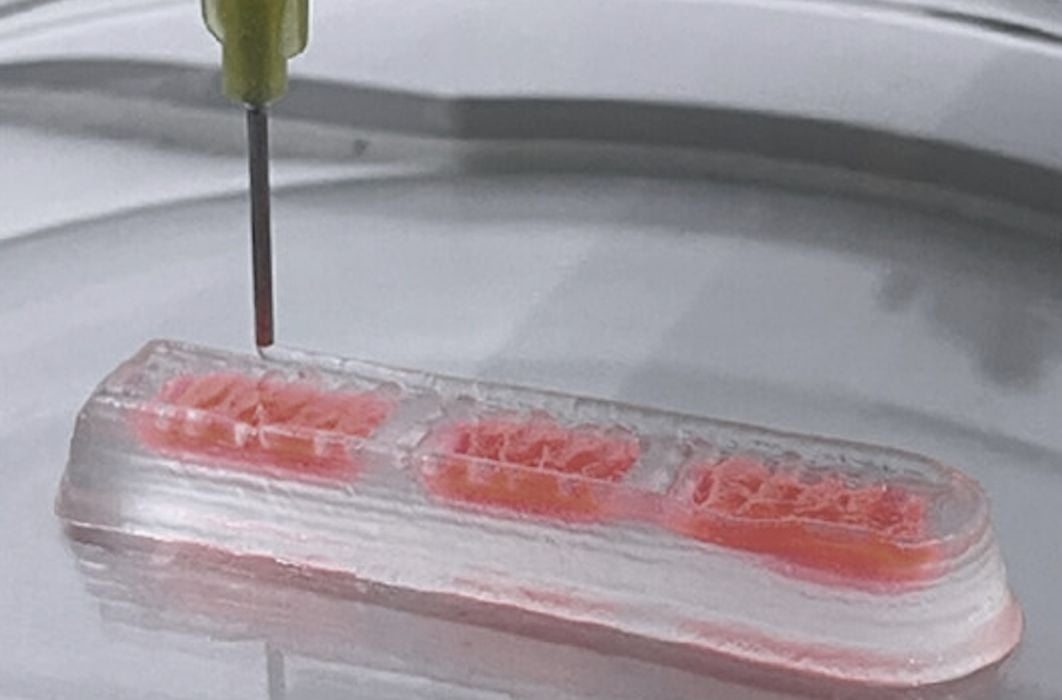

Researchers 3D Print Functional Blood Vessels Using Custom Bioink

Researchers have developed a method of 3D printing blood vessels, and that’s quite important.

New 3D Printed Blood Vessels Could Transform Heart Bypass Operations

Researchers at the University of Edinburgh have developed a method of 3D printing blood vessels.